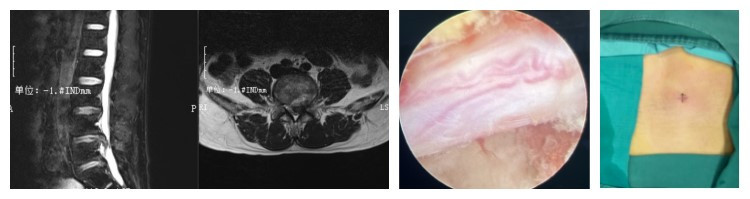

脊柱内镜(Endoscopic P/TLIF)微创治疗腰椎管狭窄症

椎间孔镜技术(PTED)治疗腰椎间盘突出症、椎间盘源性腰痛

脊柱内镜辅助下腰椎椎体间融合术(PELIF)

骨科二病区秉承着精准微创脊柱外科(AMISS)的理念,从2018年开始开展椎间孔镜技术(PTED)治疗腰椎间盘突出症、椎间盘源性腰痛及腰椎管狭窄症等,提高了我院脊柱外科微创技术水平,填补了我院脊柱内镜技术空白。2023年开始我科开展脊柱内镜辅助下腰椎椎体间融合术(PELIF)治疗退行性腰椎滑脱症及峡部裂型腰椎滑脱症(Ⅰ°~Ⅱ°)腰椎节段性不稳定合并腰椎间盘突出症、腰椎管狭窄症( 中央型椎管狭窄、椎间孔狭窄、侧隐窝狭窄)、腰椎术后不稳定等腰椎退行性疾病取得满意疗效。PELIF技术是当前脊柱外科最具代表性的微创技术,小切口大视野,创伤小,术中出血少,实现完全微创,又达到腰椎融合稳定的目的,获得广大患者认可。至此骨科二病区拥有了治疗腰椎退行性疾病的三大微创手术技术,选择和制定最适合患者病情的微创手术进行治疗达到“微创、微痕”的效果“镜”无止境。